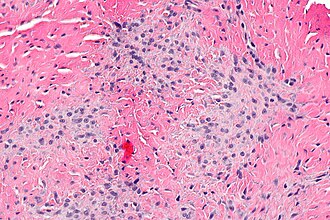

Micrograph showing a palmar fibromatosis. H&E stain.

- Bland spindle cells - typically in fascicles.

- Small thin blood vessels that are parallel to one another.

- Nuclei of blood vessels are typically darker staining than those of the lesion.